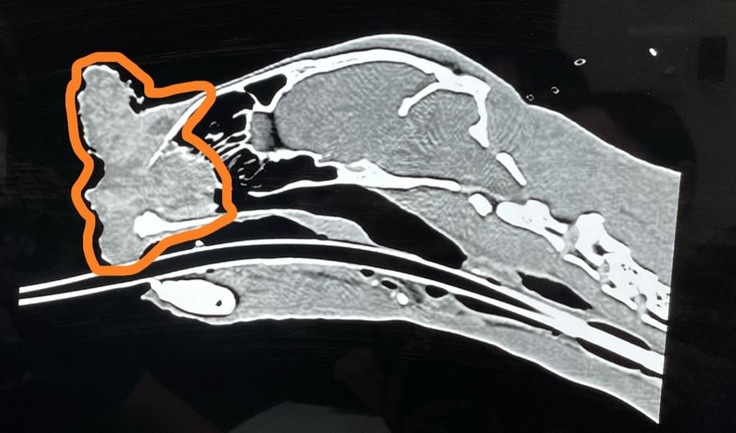

手術前に全身麻酔をかけ、CT検査と病理検査を行いました。

結果は扁平上皮癌でした。

△CT画像。オレンジの部分が癌で、鼻の奥まで浸食していることが確認できます。